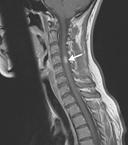

急性橫貫性脊髓炎癥狀

• 急性橫貫性脊髓炎

628健康網為您分享有關急性橫貫性脊髓炎的癥狀,急性橫貫性脊髓炎的治療方法,急性橫貫性脊髓炎的預防知識,急性橫貫性脊髓...